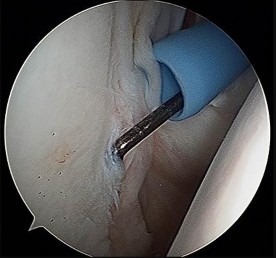

Which image seen during arthroscopic treatment is most likely associated with this patient’s condition?

An otherwise healthy 31-year-old man has had right knee pain for the past 9 months. His former physician

administered a cortisone injection and ordered 6 months of physical therapy. The patient later had an arthroscopy with debridement of the right knee by another physician and completed another course of physical therapy. The patient received minimal relief from these treatments and still is not able to walk longer distances or go on hikes. On examination, he is a healthy appearing male with a body mass index of 24 kg/m2. He has a small effusion, minimal quadriceps atrophy, no tenderness about the knee, full range of motion, stable to varus and valgus stress at 30° of flexion, a grade 1 Lachman test, and a normal posterior drawer. Figures 1 through 4 are his arthroscopic views, radiograph and MRI scan from his prior surgical procedure. What is the next most appropriate step in treatment?